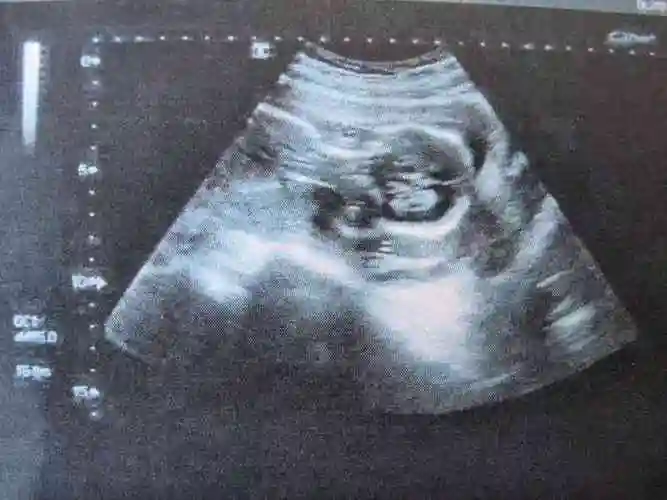

脊柱串珠是女宝平行排列是男宝的说法是真的吗